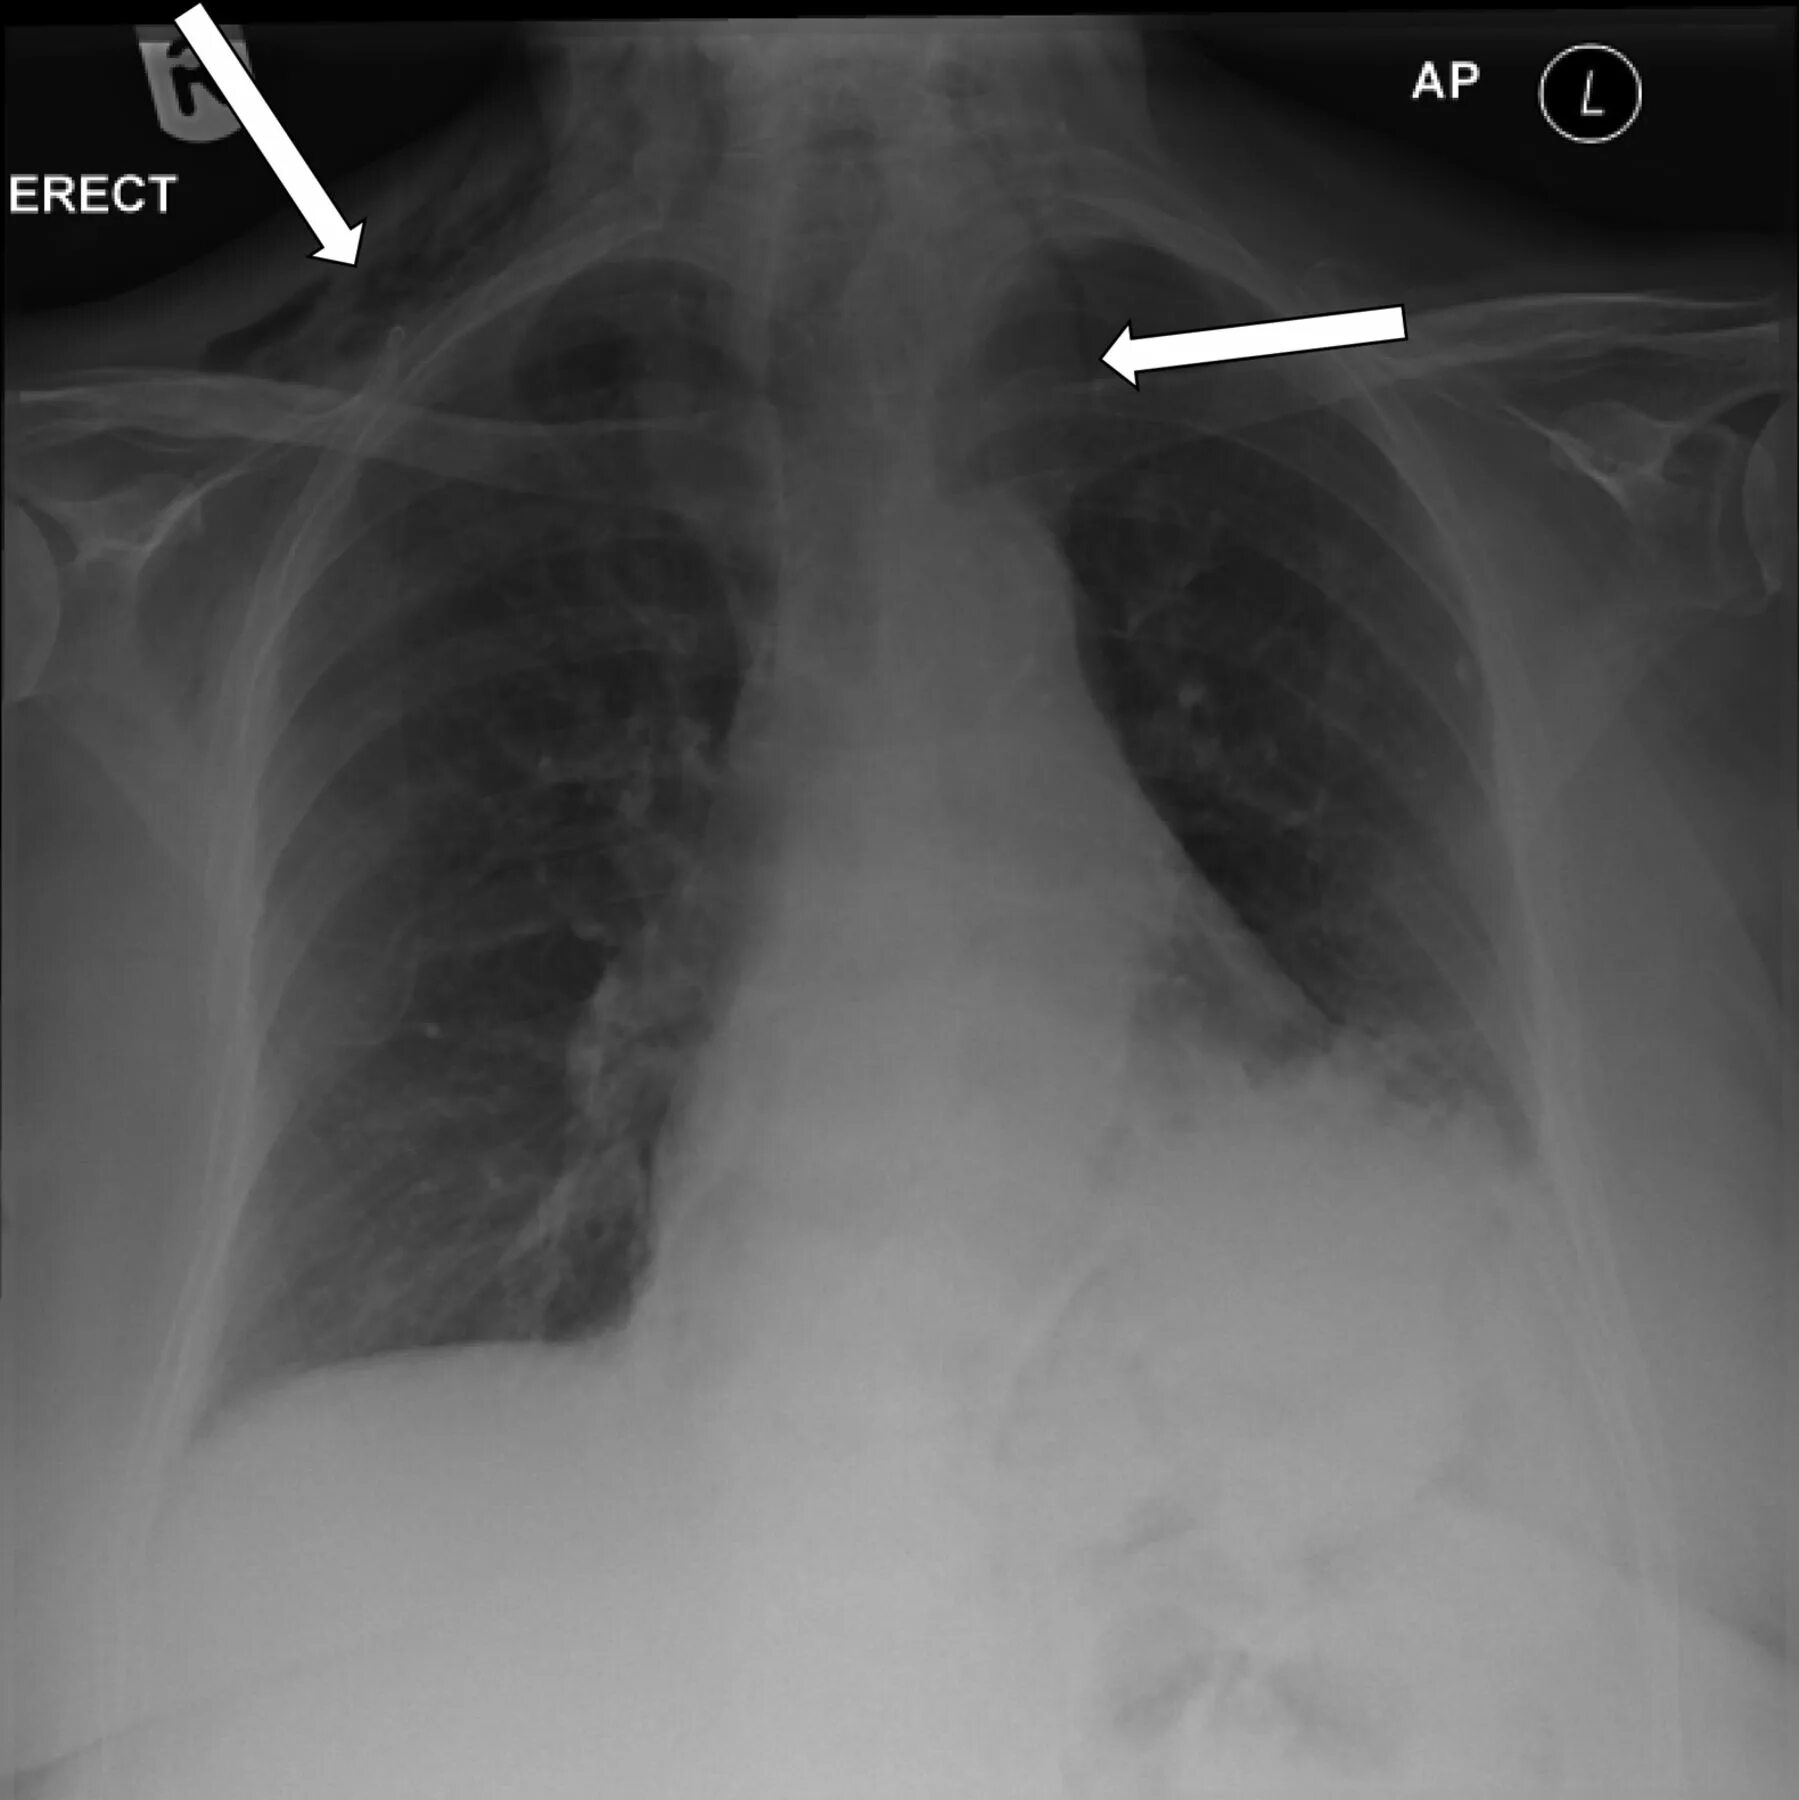

Эмфизема мягких